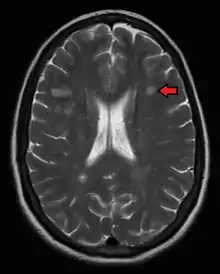

The name multiple sclerosis refers to the scars (sclerae – better known as plaques or lesions) that form in the nervous system. These lesions most commonly affect the white matter in the optic nerve, brain stem, basal ganglia, and spinal cord, or white matter tracts close to the lateral ventricles.[1] The function of white matter cells is to carry signals between grey matter areas, where the processing is done, and the rest of the body. The peripheral nervous system is rarely involved.[9]

To be specific, MS involves the loss of oligodendrocytes, the cells responsible for creating and maintaining a fatty layer—known as the myelin sheath—which helps the neurons carry electrical signals (action potentials).[1] This results in a thinning or complete loss of myelin, and as the disease advances, the breakdown of the axons of neurons. When the myelin is lost, a neuron can no longer effectively conduct electrical signals.[9] A repair process, called remyelination, takes place in early phases of the disease, but the oligodendrocytes are unable to completely rebuild the cell's myelin sheath.[62] Repeated attacks lead to successively less effective remyelinations, until a scar-like plaque is built up around the damaged axons.[62] These scars are the origin of the symptoms and during an attack magnetic resonance imaging (MRI) often shows more than 10 new plaques.[1] This could indicate that some number of lesions exist, below which the brain is capable of repairing itself without producing noticeable consequences.[1] Another process involved in the creation of lesions is an abnormal increase in the number of astrocytes due to the destruction of nearby neurons.[1] A number of lesion patterns have been described.[63]

Magnetic resonance imaging (MRI) of the brain and spine may show areas of demyelination (lesions or plaques). Gadolinium can be administered intravenously as a contrast agent to highlight active plaques, and by elimination, demonstrate the existence of historical lesions not associated with symptoms at the moment of the evaluation.[70][71]